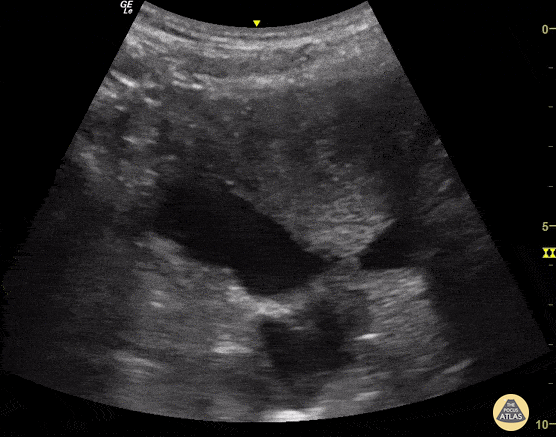

Trauma - Free Fluid within Abdomen

A 35-year-old woman presented to the ED after experiencing blunt abdominal trauma. She was hemodynamically unable. E-FAST Exam performed at bedside was notable for free intra-abdominal fluid (viewed here from suprapubic region). This rapid diagnosis enabled prompt disposition to the operating room. Josiane Almeida, Emergency Physician; Sao Paulo- Brazil